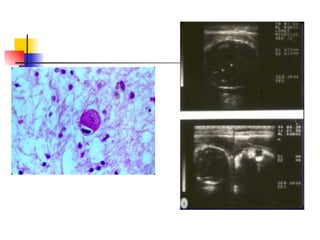

DIAGNÓSTICO: Directo : citológico: células gigantes multinucleadas(citodiagnóstico de Tzanck) Antígeno por IF en raspado de base de vesículas. Aislamiento en Hep-2, riñón de conejo ó humano. Identificación en shell vial +IF :más rápido y más sensible.  PCR. Indirecto :  seroconversión para IgG en 2 muestras pareads. IgM específica.

Citodiagnóstico de Tzanck

DIAGNÓSTICO: Directo :citológico: células gigantes multinucleadas(citodiagnóstico de Tzanck) Antígeno por IF en raspado de base de vesículas. Aislamiento en Hep-2, riñón de conejo ó humano. Identificación en shell vial +IF :más rápido y más sensible. PCR. Indirecto : seroconversión para IgG en 2 muestras pareads. IgM específica.